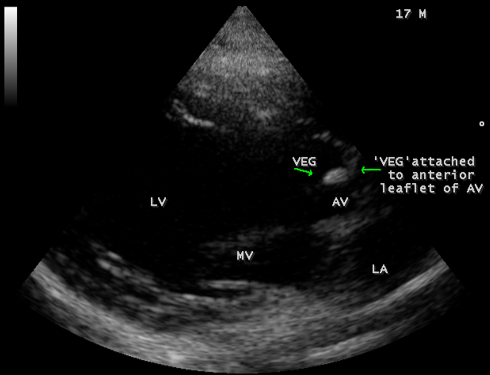

A 17-year-old female was brought to the emergency room with a history of sudden onset of breathlessness. Her pulse rate was 87 bpm and blood pressure 110/60 mmHg. She had a history of rheumatic fever during childhood, an episode of febrile illness for 10 days and taken antibiotic treatment recently. Blood chemistry revealed normal and blood cultures were negative. ECG revealed normal as shown in Figure 1 and X-ray chest revealed dilated LV (left ventricle) as in Figure 2. Physical examination revealed grade 3/6 early diastolic murmur over left mid sternal border, basal crackles over lung fields and no peripheral signs of wide pulse pressure. Transthoracic echocardiography revealed vegetations on anterior and posterior leaflets of aortic valve as in Figure 3 and Figure 4, with a “kissing-type “as in Figures 5, 6 and 8. The aortic valve was bicuspid with an attached vegetation as in Figure 9 and it was severely regurgitant as in Figure 10 and Figure 11. The left ventricle is dilated as in Figure 12 with moderate LV dysfunction as in Figure 13. The thoracic aorta was prominent as in Figure 14 with a ‘holodiastolic flow reversal’ as in Figure 15. The patient was treated with digoxin (0.25 mg, half daily), diuretics (Injection. Furosemide 20 mg IV twice daily), ACE inhibitors (tablet. Enalapril 2.5 mg twice daily) along with 2 weeks course of intravenous (IV) cefotaxime (1g) and amickacin (500mg) twice daily and advised aortic valve replacement at the earliest with lifelong penicillin prophylaxis and continuation of antibiotics for 6 weeks since the vegetations remain stable after 2 weeks of treatment, but without any embolic episodes.

Figure 3: Parasternal long axis view showing the vegetation on the anterior leaflet of aortic valve (arrows) in a 17-year old female.